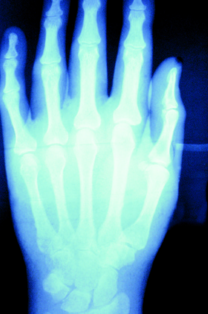

Dorsal Dislocation

Matthew J. Letizia, DO; Marcin K. Kociuba, DO; James Lundy, DO

<div id="article-content-body"> <p>Several hours after striking his closed fist against the side pillar of a passenger car, a 28-year-old man presented with acute pain and swelling of...